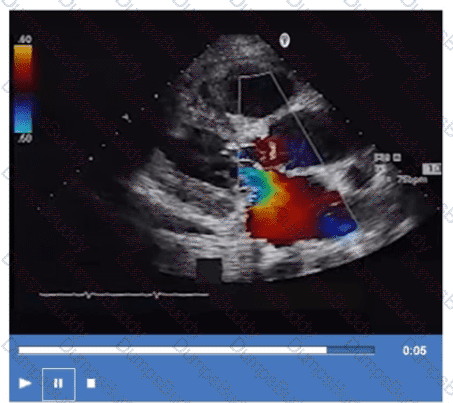

Which of the following measurements is required for calculating the Qp/Qs ratio?